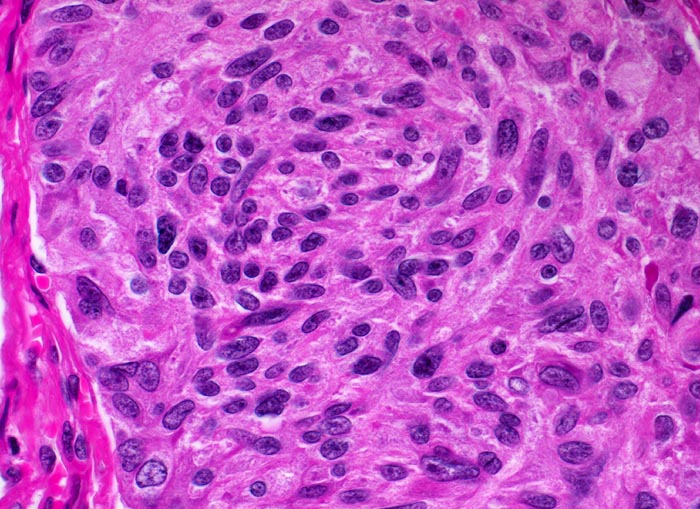

Das MTC metastasiert primär in die lokoregionären Lymphknoten. Bei 15% der Patient*innen liegen zum Zeitpunkt der Diagnose bereits Fernmetastasen in Lungen, Leber oder Knochen vor. Histologisch sind die Tumoren meist solide und bestehen aus monomorphen polygonalen und spindeligen Zellen (> 3821). Die Zellkerne zeigen das typische Pfeffer und Salz Chromatin neuroendokriner Zellen. Das Stroma enthält in ca. 50% der Fälle Amyloid.

• Die Tumorinfiltrate bestehen aus soliden und kribriformen Verbänden spindeliger Tumorzellen.

• Tumorzellen mit überwiegend monomorphen Zellkernen mit feinkörnigem Pfeffer und Salz Chromatin (Merkmal endokriner Zellen). Nukleolen sind nicht prominent. Reichlich eosinophiles Zytoplasma.